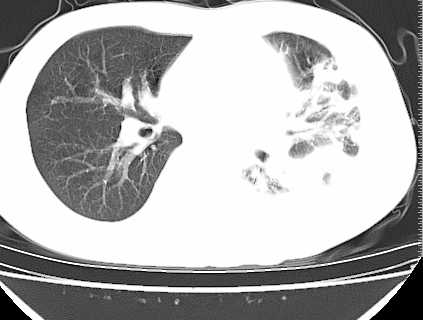

左下肺见有较多斑片状和大片状影,支气管通畅,左侧胸腔积液,考虑:左下肺炎伴胸腔积液

左肺下叶大叶性肺炎。左侧胸腔积液。年龄?最好化验一下血象。血沿沉。

患者刺激性干嗽,无咯血,伴心悸,低热,夜间无明显盗汗,消瘦明显,左侧中量胸腔积液伴左肺下叶肺膨胀不全、上肺外围多个小斑片病灶。考虑肺结核可能性大。

左肺舌叶及下叶见斑片状,大片状高密度影并相应处胸膜及心包不规则增厚,左肺下叶膨胀不全。右肺未见异常,双肺段以上支气管通畅。纵隔左移,其内未见明显肿大淋巴结。左侧胸腔积液。

1.考虑:左肺化脓性炎症。2.左侧胸腔积液(中等量)。3.心包炎症。